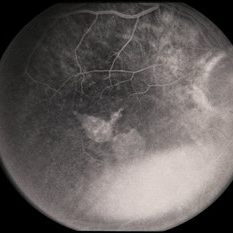

---thumb.jpg/image-square;max$300,300.ImageHandler) Age Related Macular Degeneration - Geographic Atrophy

Age Related Macular Degeneration - Geographic Atrophy

May 3 2013 by Suber S. Huang, MD, MBA, FASRS

Geographic Atrophy.

Imaging device: Retina Diseases Imaging Reading Center

Condition/keywords: advanced geographic atrophy, atrophic scar, atrophic spot, geographic atrophy, macula lesion, pigment epithelial atrophy, red-free, window defect